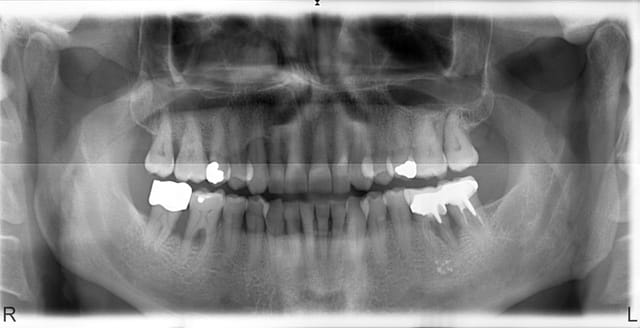

Merci pour vos avis

ci joint le pano pris jeudi

donc pour recapituler

pano initial : mars 2008

detartrage, apprentissage techniques hyhiènes, stoppage du broxodjette en direction des apex patience tel ceramik l'a suggeré

équilibration occlusale :grosses interferences NT bien vu Nolive

j'ai été conservateur désolé nolive et Pluton des 46 47 (mais jusqu'à quand)

Merci aussi cousin pour tes avis

aucun materiau de comblement comme Jeamba (promis pour la furcation de 46 c'est pas du photoshop) ni de separations qui demande à mon humble avis une (trop) grande coopération du patient

Sans faire de pub pour l'implant mais plutôt pour le concept switching Platform, j'aime bien le design, le niveau osseux stable qui sont des constantes pour ce systeme

L'extraction a eu lieu le jour du pano

l'implant 40 jours après

pano de controle 2 ans et 9 mois plus tard avec un contrôle detartrage tous les 9 mois environ

Je pense gicler la 27 l'année prochaine si la météo est favorable